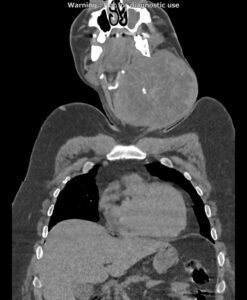

در سی تی اسکن اسپیرال از گردن ، ریه و مدیاستن با و بدون تزریق (مولتی دیدکتور 16 با مقاطع ظریف و بازسازی های ساژیتال و کرونال):

بیمار آقای 44 ساله با توده گردنی جهت بررسی بیشتر، مراجعه نمودند:

تصویر توده بزرگ به ابعاد 118x133mm در پلن آگزیال و دیامتر کرانیو کودال 126mm در سمت چپ گردن با نمای هتروژن و کلسیفیکاسیون Coarse مرکزی رویت می شود. به نظرمنشا توده ذکر شده از لوب چپ تیروئید می باشد. گسترش فوقانی توده تا سطح مهره دوم گردنی و زیر زاویه مندیبل و گسترش تحتانی آن تا ناحیه سوپراکلاویکولار بدون گسترش اینتراتوراسیک رویت می شود.

دو لنف آدنوپاتی سنترال چپ (zone 6) با حداکثر SAD=16mm مشهود است.

تعدادی لنف نود کوچک در زون های لترال دو طرف با ابعاد غیرپاتولوژیک مشهود است.

اثر فشاری توده ذکر شده به تراشه با انحراف آن به سمت مقابل رویت می شود.

اثر فشاری توده ذکر شده به ورید ژوگولارداخلی و CCA با جابه جایی خلفی و به SCM با جابه جایی خلفی لترال آن مشهود است.

مجموع یافته ها مطرح کننده توده تیروئید با اثرات ذکر شده می باشد.